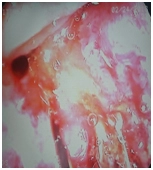

Колоноскопия

В области поперечной ободочной кишки определяется крупное стенозирующее циркулярное образование до 5 см, суживающее просвет кишки до 1 см, выражено контактно кровоточит, с трудом проходимо аппаратом. Выполнена биопсия на гистологическое исследование (с помощью струны-проводника для лучшего позиционирования аппарата).

Гистологическое исследование образования толстой кишки.

В одном из представленных фрагментов – фиброзная ткань с комплексами инфильтративной муцинозной аденокарциномы (G1).